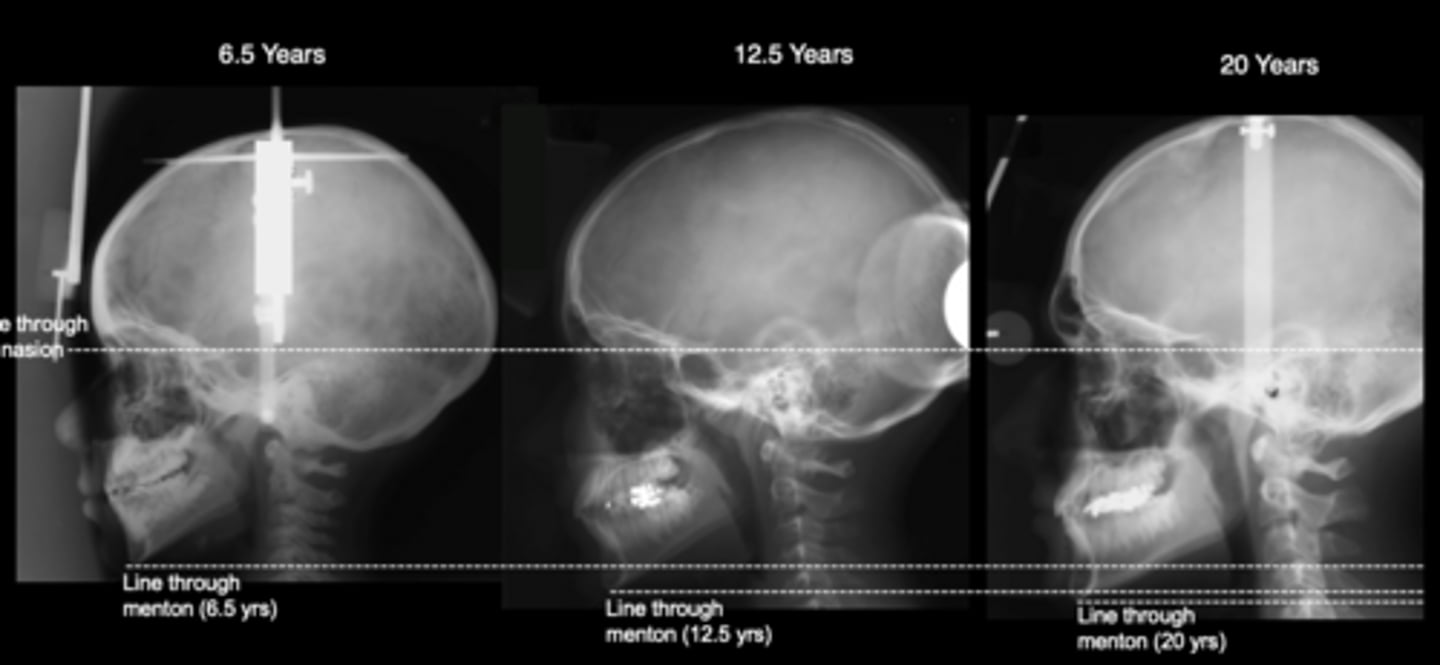

the cranial base and facial skeleton follow different patterns of growth cessation

A key principle in application is that

cessation of neurocranial growth

The facial skeleton continues to grow long after the

superior-inferior

The cranial base establishes a ____________________ gradient of growth cessation